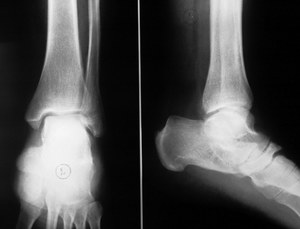

Диагностика

Рентгенография. Этот метод диагностики применяется при подозрении на травмы связок голеностопного сустава. Он помогает различить переломы костей и разрывы связок. Рентгенографию проводят в боковой и прямой проекциях. Это исследование является обязательным;